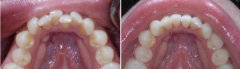

牙齿不齐怎么办?

随着现代口腔医疗技术的发展,牙齿不整齐 的问题也可以得到矫正,让牙齿重...【详细】

活动牙齿矫正需要注意什么事项?

牙齿在生长发育过程中,由先天的遗传因素或后天的环境因素,如疾病、口腔不...【详细】